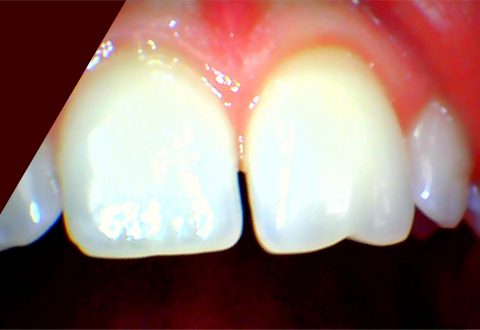

Из-за широкого промежутка между зубами, люди не только стесняются своей улыбки! Это лишь малая часть айсберга всех проблем, которые щель между зубами может принести.

Диастема (так она по врачебному называется) ведёт к неправильной жевательной нагрузке, давящей на зубы! Просто представьте, что у бобра или белки между их огромными и острыми, как бритва зубами, располагается огромная щель! Да они ни один орех не раскусят и ни один древесный ствол не разгрызут, а вот зубы повредят!

Тоже самое примерно происходит и у человека. Зубы на пищу давят неравномерно, отсюда и повреждения, такие например, как сколы, один из которых Вы можете увидеть на картинке!

Пациенту была закрыта диастема и восстановлен зуб на режущем крае после произошедшего скола.

Фотография предоставлена врачом стоматологом-терапевтом – Разживиной Еленой Сергеевной